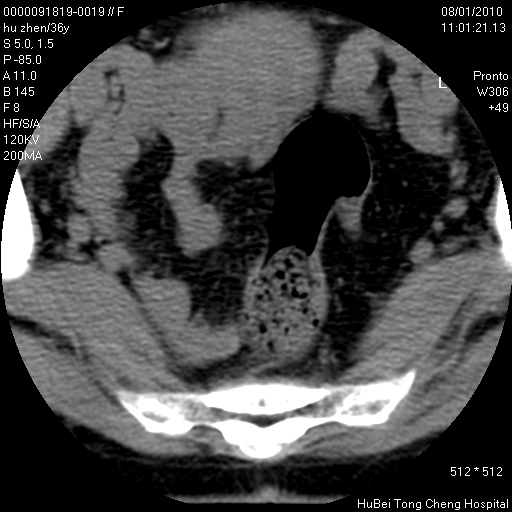

患者 女,36岁。右侧腰腿痛半月余。腰骶椎mr平扫偶然发现骶椎异常信号。

临床诊断:1)腰椎间盘突出症。2)骶椎肿瘤性病变?

骶椎ct平扫(层厚、层距均为5mm),图像如下: